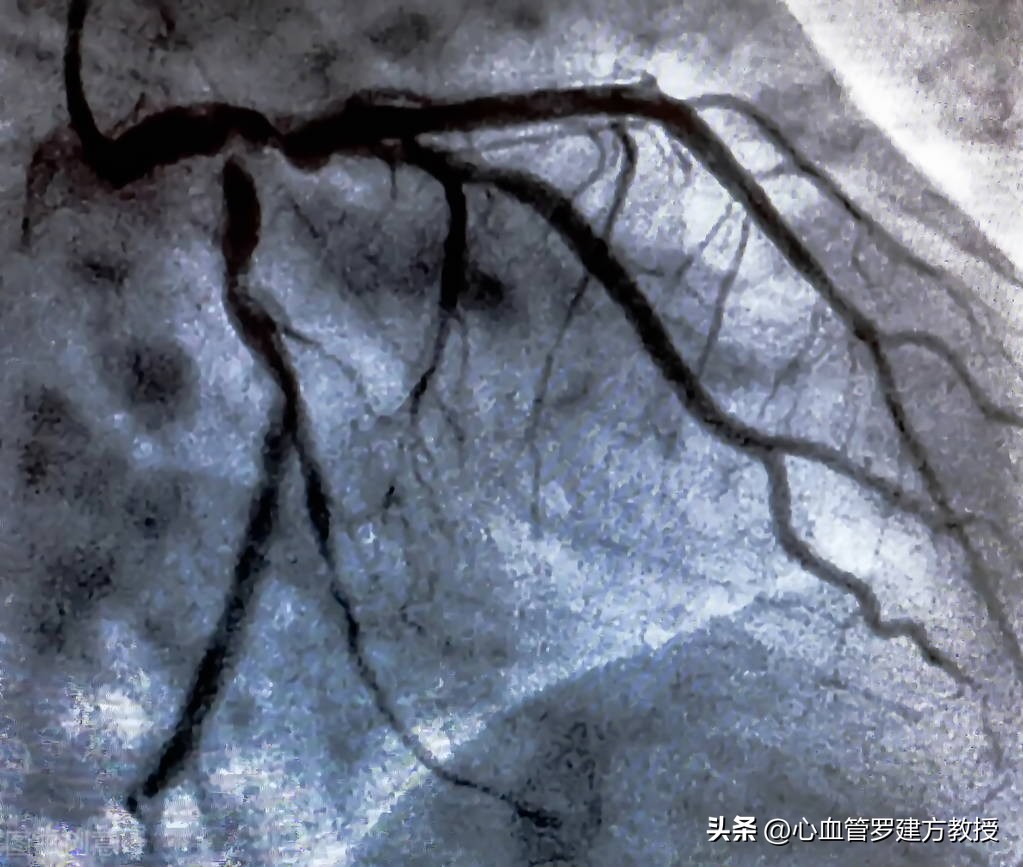

冠脉造影需要从外周大动脉进导管,一般来说,会选择股动脉或者是桡动脉来插入导管直至主动脉根部,再选择性地将导管送入左冠或者右冠状动脉开口,注射入造影剂,再通过X线透视下来显示整个冠脉的形态特点。通过冠脉造影术可以直接看到心脏血管里面有没有病变,是否存在有堵塞的情况,具体的病变堵塞的严重程度怎样,冠脉造影是目前诊断冠心病最直接也最可靠的方法,它能非常清楚的显示冠脉有无狭窄,其狭窄的部位、狭窄程度、范围以及病变处血管的血流情况等等,医生可以根据冠脉造影的结果,再进一步的指导后续的治疗措施和方案。冠脉造影是国内外公认的诊断冠心病的“金标准”。